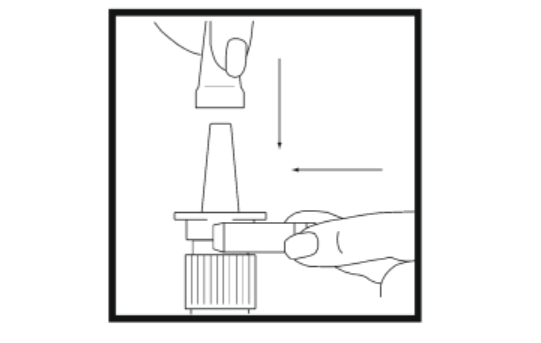

2. Remove the safety clip and clear plastic dust cover from the spray bottle.

3. Clean the tip of pump. Hold the bottle in a horizontal position and rinse the spray

tip with warm water, while wiping the tip with your finger or a clean soft cloth.Do not clean the spray tip with a pointed object. This could cause an improper dose

of the spray to be delivered. Do not remove the pump from the bottle, as this will

release the priming pressure.Wipe the tip dry with a clean soft cloth or tissue.

10. Replace the safety clip and the clear plastic dust cover on the spray bottle.